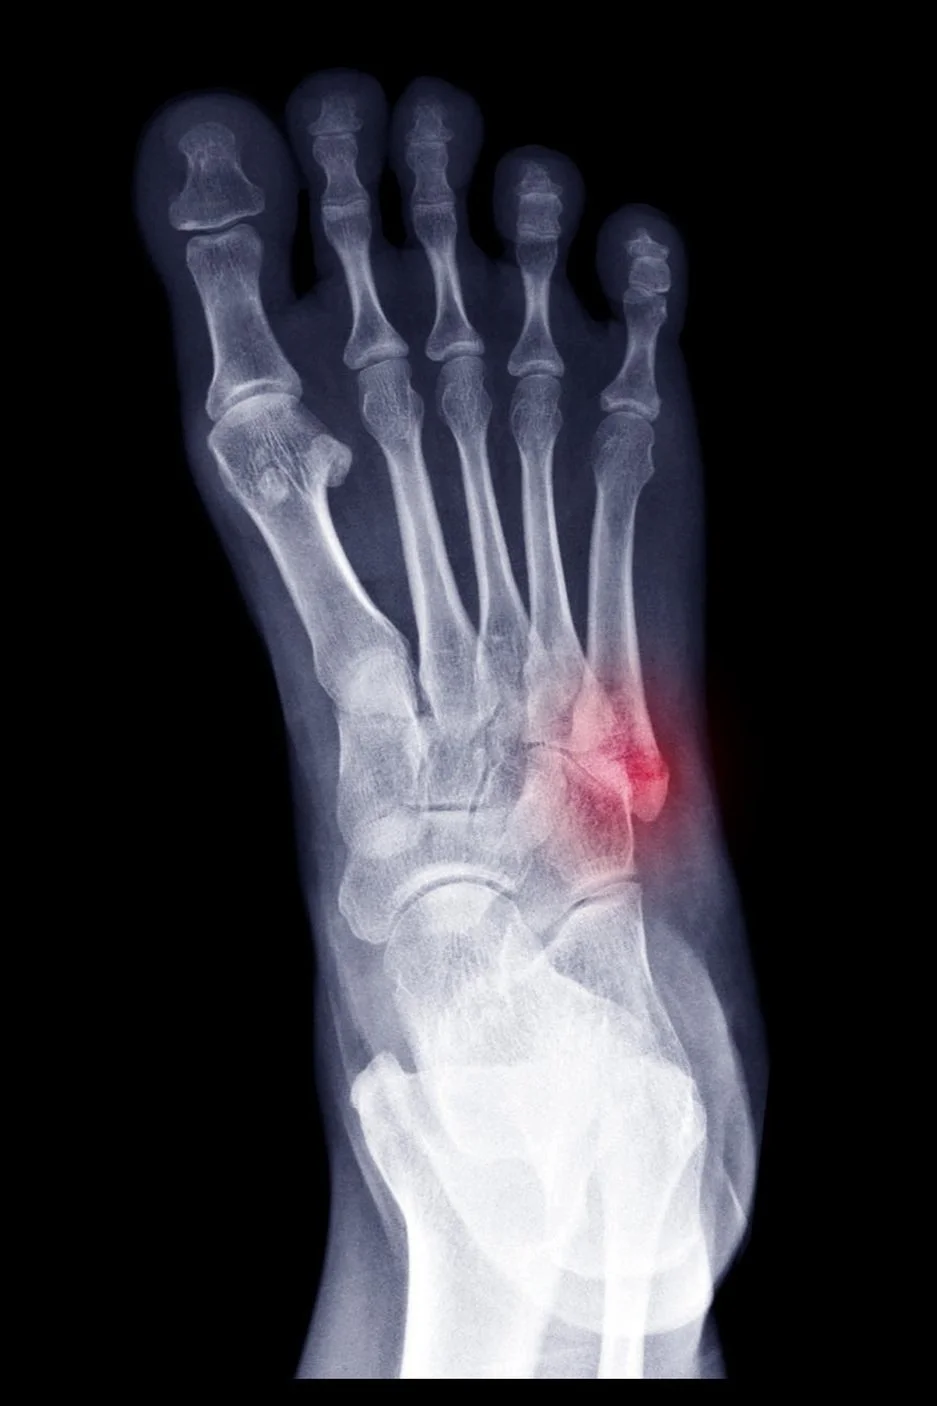

X ray radiograph show toe bone broken (base of metatarsal fracture or Jones fracture). Highlight on fracture site and painful area